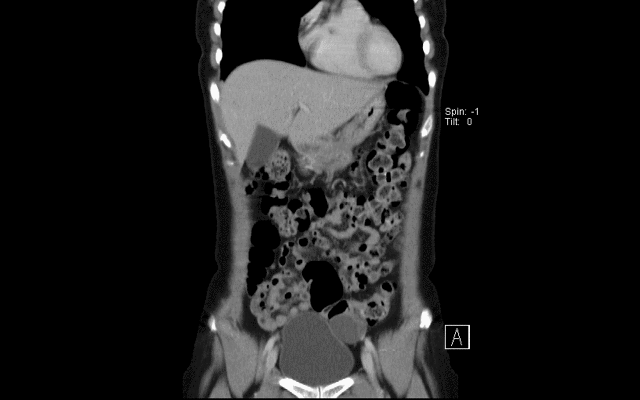

43F, right flank pain

POCUS: right moderate hydronephrosis & peri-renal fluid

trace dilated ureter to UVJ

No hydronephrosis on left side

Splenic tumor noted over lower pole of spleen

KUB: no obvious stone

CT: right hydronephrosis, splenic lesion, R UVJ stone